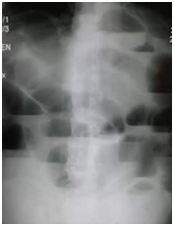

西醫(yī)答辯例題1:【臨床判讀】根據(jù)下面X線片判斷臨床意義。(5分)

【正確答案】 參考答題要點(diǎn):單純性小腸梗阻。

單純性小腸梗阻是小腸內(nèi)容物運(yùn)行障礙所致的急腹癥。典型臨床表現(xiàn)為腹痛、腹脹、嘔吐。腹部立位片顯示腹腔內(nèi)多發(fā)階梯狀氣液平面。

【該題針對(duì)“X線片”知識(shí)點(diǎn)進(jìn)行考核】